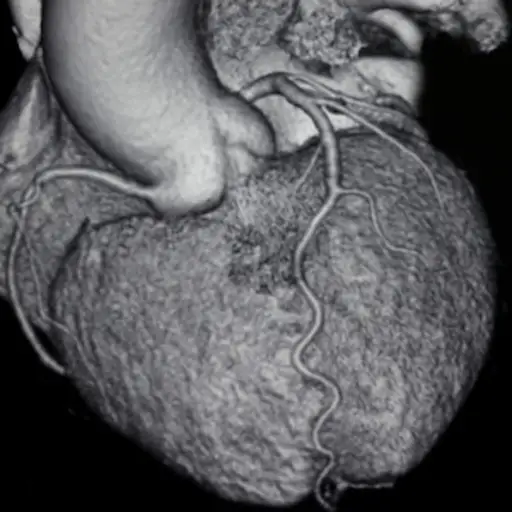

CT扫描

计算断层扫描(CT)通过使用多层扫描仪采用高分辨率X射线图像来执行扫描。这种先进的成像可以检测冠状动脉疾病,评价先天性心脏病,并且可用于在复杂的导管消融程序之前评估患者的心脏。